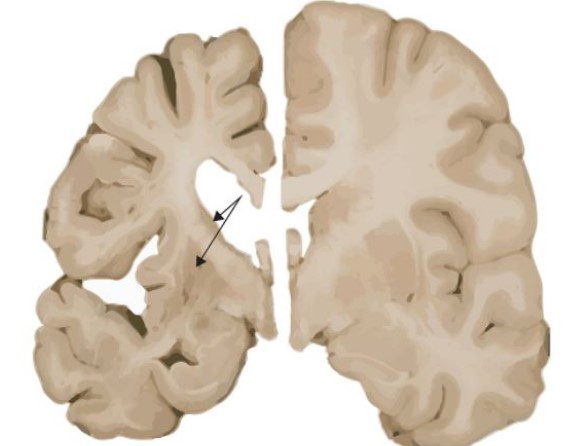

이러한 과도한 반복은 비정상적인 헌팅틴 단백질을 생성하며, 이 단백질은 뇌의 특정 신경세포에 손상을 입혀 점차적으로 죽음을 초래합니다.

헌팅턴병의 증상은 크게 운동, 인지, 정서 장애로 나눌 수 있습니다.

운동 장애 : 불수의적인 움직임 (클로레아): 몸이나 얼굴의 갑작스런, 빠르고, 불규칙한 움직임.

조정 장애 : 걷기, 균형 유지, 정교한 운동 수행에 어려움. 근육의 강직과 운동 둔화.

인지 장애 : 집중력과 주의력 저하. 기억력 감소 및 학습 능력 저하. 판단력 및 문제해결 능력 손상. 진행되면서 인지적 능력 전반에 걸쳐 저하. 정서 장애: 우울증: 가장 흔한 정서적 문제로, 불안, 슬픔, 무관심을 포함합니다.